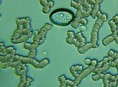

Mnohé štúdie dokazujú pozitívny efekt Bioquantu - jeho laserového žiarenia na postupnú elimináciu baktérií, vírusov či lariev parazitov migrujúcich v krvnom riečišti. Ide najmä o normalizáciu imunity, špecifickej i nešpecifickej. Navyše termodynamický efekt laseru pri ožarovaní krvi, ktorý síce náš organizmus nevníma a ľudské bunky neohrozuje, spôsobuje zvyšovanie termodynamickej teploty najmenších štruktúr - teda mikroorganizmov. Tieto následne ničí aktivovaná imunita a zvýšená baktericídna aktivita krvného séra. Sú zaznamenané pozitívne efekty pri vírusoch HIV/AIDS, vírusoch encefalitídy, pri borelióze, pri prevencii chrípky. O účinkoch na baktérie svedčí aj vysoká účinnosť pri výskytu akné baktérií. Prostredníctvom aktivácie porfírinov sa uvoľňujú voľné radikály a tým zabíjajú baktérie zvnútra..

Laserové ožarovanie krvi navodzuje i úpravu pomerov populácie T helperov a T supresorov smerom k normalizácii a úprave celkového počtu T lymfocytov a vyvoláva zmenu aktivity enzýmov imunokompetentných buniek. To je dôležité pre celom rade ďalších ochorení.